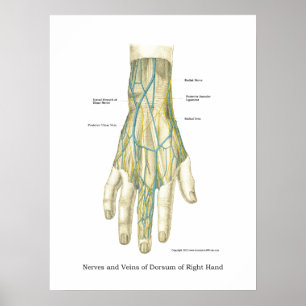

Poster interno da anatomia da mão & do pulso

Preço48,95 €